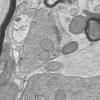

Neuroaxonal dystrophy (3)